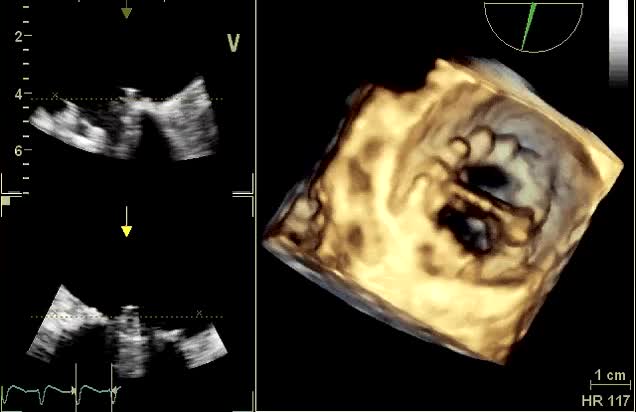

Tecniche cardiochirurgiche di riparazione della valvola tricuspide